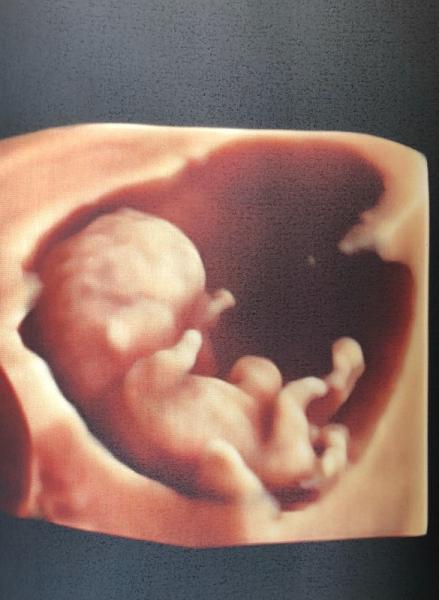

Und das zweite Bild

Bild zu

oh toll, wie viel man sieht!

Wahnsinn oder. Es ist auf einmal so groß, dass der Arzt nicht mehr doll den US vergrößern muss

Wow tolle Bilder freut mich dass alles gut ist. Hab meinen nächsten Termin in der 14. Ssw, das ust noch soooo lang hin

Warst du beim selben Arzt? Habe heute auch 3 Bilder erhalten die fast genauso aussehen, also 2D und 3D :D:D Die Nackenfaltenmessung wollten wir auch nicht machen lassen. Das Ergebnis ist ja nur zu 75% sicher und dann macht man sich am Ende nur verrückt bis das Ergebnis vom Bluttest da ist und es ist gar nix! Jedenfalls meinte meine Ärztin heute auch, dass obwohl wir die Messung nicht wollen sie uns beruhigen kann: die Falte wäre so klein, die würde sie auch nicht messen wollen Darf mans jetzt eigentlich in die Welt hinausschreien? Bin jetzt 11+3 und mein nächster Termin ist in 5 Wochen und langsam aber sicher kann ich’s nur noch in weiten Klamotten verstecken

Wow, was für ein Bild!!! Ich mag auch so was haben

Was für ein wahnsinns Bild... toll!

Hey du ... Diese 3 D Bilder sind ja der Hammer Ich habe in der 14. Woche mal ein Kind verloren und da stand das Genital auch heraus. Auf die Rückfrage bei meinem Arzt meinte dieser, dass erstmal alle Genitalien hervor stehen und man selbst in der 14. Woche das Geschlecht nicht definieren kann... Es scheint also alles offen bei dir zu sein